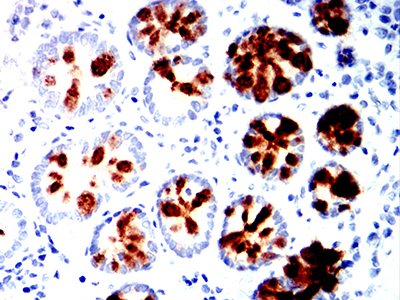

Immunohistochemical analysis of paraffin-embedded human colon tissues using MUC2 mouse mAb with DAB staining.

Immunohistochemical analysis of paraffin-embedded human stomach cancer tissues using MUC2 mouse mAb with DAB staining.